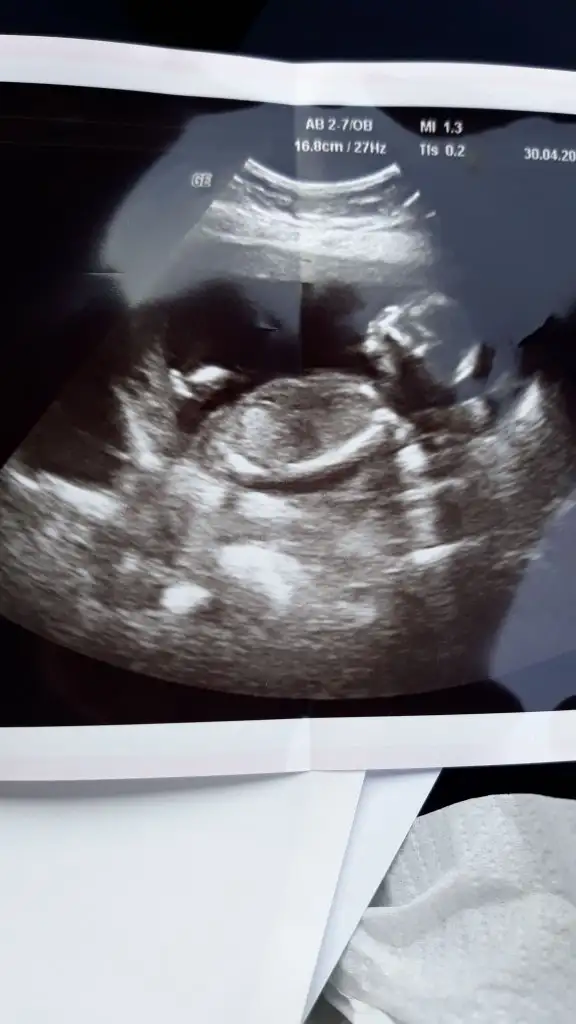

Kaç haftalık 11 12 13 hafta olmalı sanki buyuk usg tekrar usg paylaşırsınız sanki kız gibi

O usg de 16 haftalikti malesef sizin dediginuz hafyalarda gidemedim salgin yuzundenKaç haftalık 11 12 13 hafta olmalı sanki buyuk usg tekrar usg paylaşırsınız sanki kız gibi

Sanki kız gibi geldi bana dr söylemedimiO usg de 16 haftalikti malesef sizin dediginuz hafyalarda gidemedim salgin yuzunden

Yok dr bisey demedi goremiyorum dediSanki kız gibi geldi bana dr söylemedimi